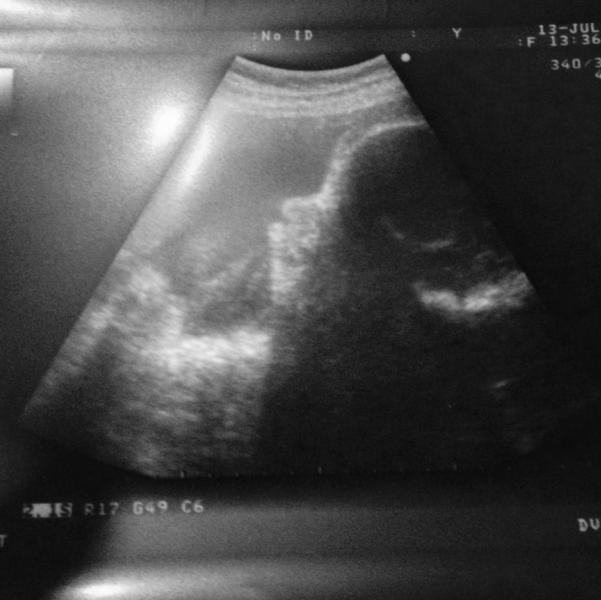

Сходили сегодня на 3 УЗИ. Поставили мне все- таки диагноз симфизит, расхождение костей на 6 мм. В пределах нормы, но плод крупный, она по развитию на 35 недель сейчас, а у меня только 33. Вес 2400. Врач, которая делала УЗИ, сказала, что скорей всего будут кесарить( А так хотелось ЕР( Расстроилась короче вообще. Сказали обязательно носить бандаж и мазь прописали. Еще спрашивают на приеме - а чего раньше не стали бандаж носить. А откуда ж я знаю, что нужно уже? Мне врач мой не говорила, а ходить ...